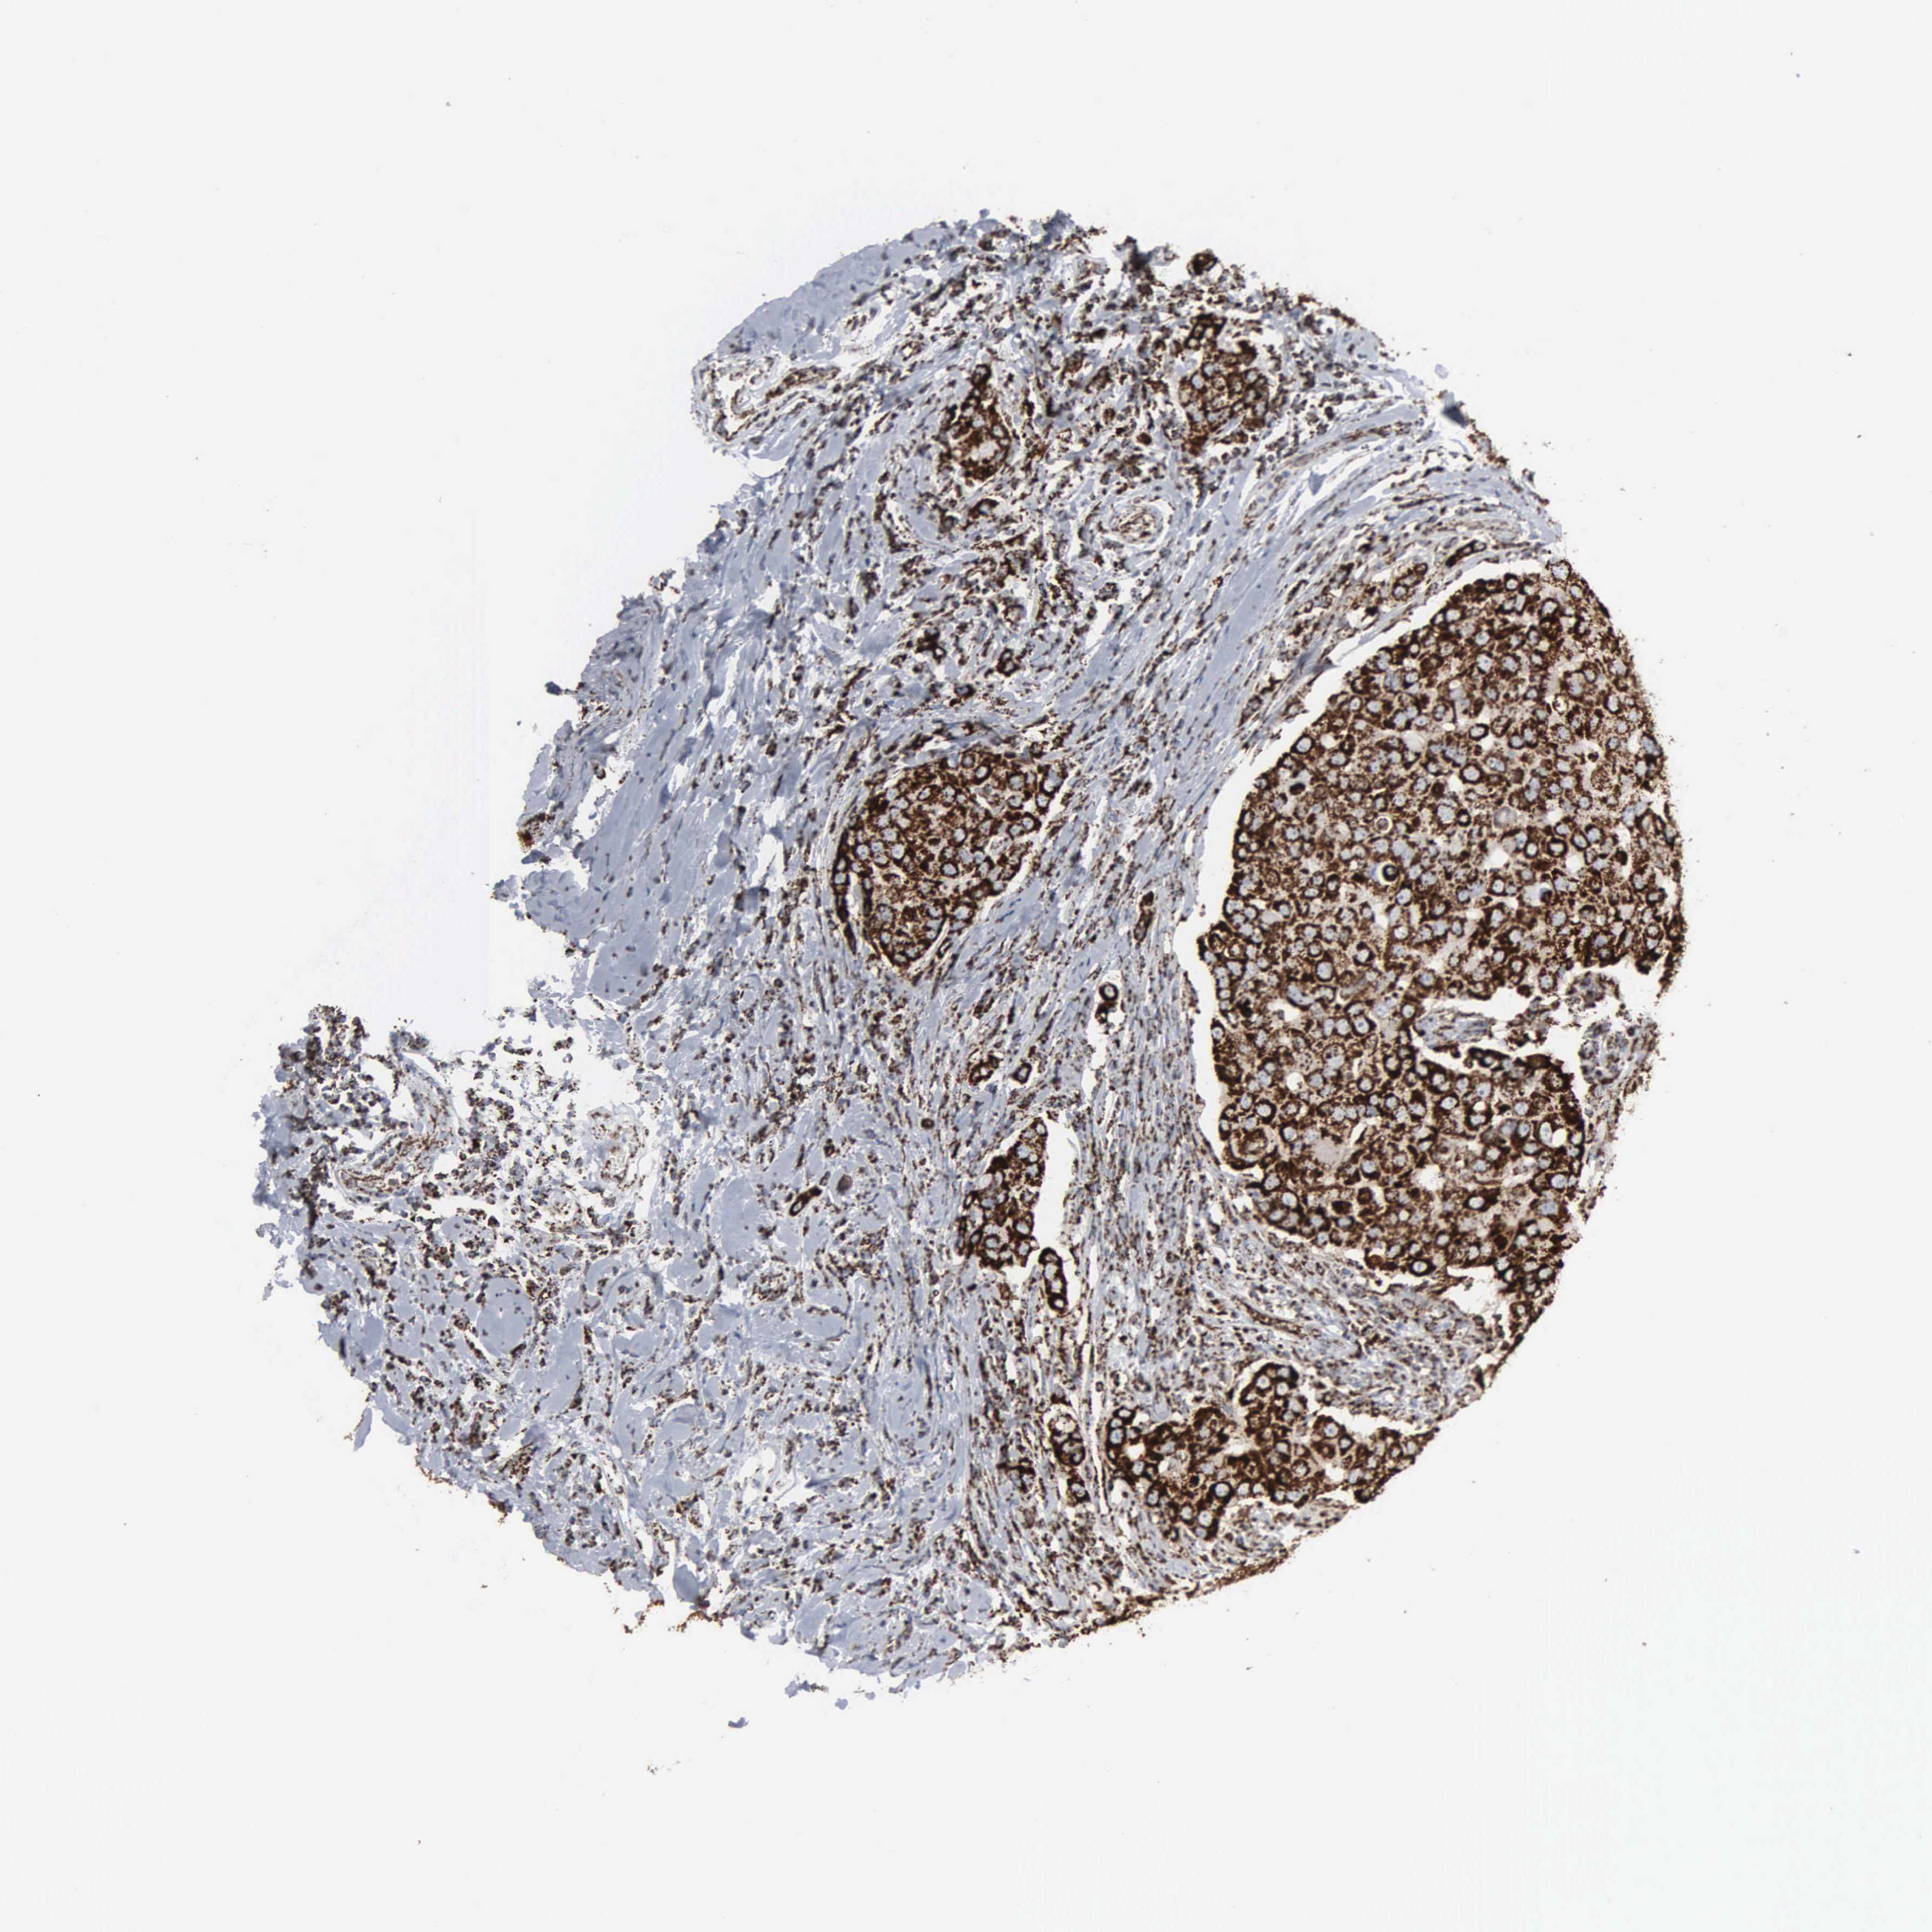

CANCER BREAST CANCER Show tissue menu

BRCA TCGA BRCA VALIDATION PROTEIN EXPRESSION